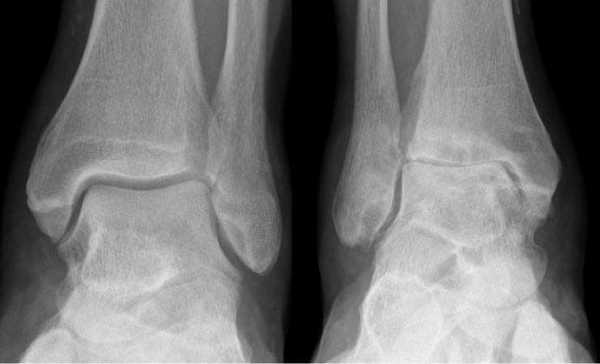

Остеоартроз голеностопного сустава на рентгене.

Остеоартроз левого(справа на снимке) голеностопного сустава

Рентгенологические стадии по Kellgren и Lawrence:

- 0 — полное отсутствие рентгенологических признаков;

- І — кистовидные изменения костной ткани, субхондральный линейный остеосклероз, краевые остеофиты небольшого размера;

- ІІ — сужение суставной щели, более выраженный остеосклероз;

- ІІІ — массивный субхондральный остеосклероз, сильное сужение суставной щели, остеофиты большого размера;

- ІV — массивные остеофиты, деформация эпифизов костей, практически полное отсутствие суставной щели.

- Начальная стадия. Характеризуется поражением только суставных хрящей. На рентгенограммах может визуализироваться незначительное сужение суставной щели, которое заметно лишь при сравнении с симметричным суставом.

- Стадия выраженных изменений. В дегенеративно-деструктивный процесс вовлекаются кости с развитием субхондрального остеосклероза. При рентгенографии выявляют краевые остеофиты и неравномерное сужение суставной щели как минимум на 50%.

- Стадия ярко выраженных изменений. Проявляется выраженным ограничением подвижности голеностопа. На рентгенограммах видны большие участки остеосклероза, массивные остеофиты, деформация костей и нарушение конгруэнтности суставных поверхностей.